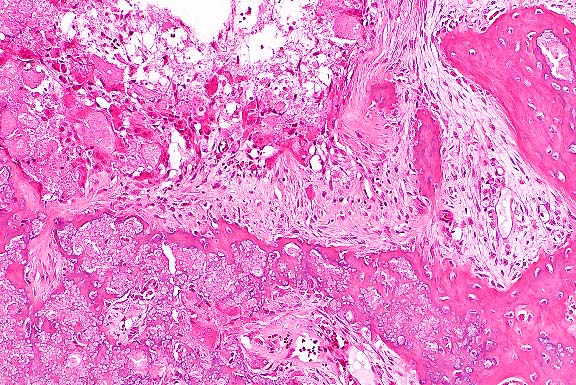

- Microscopically, necrosis and fibrinopurulent debris

are prominent at the level of the distal growth plate of the

metacarpal bone. Mature and fragmented neutrophils are common,

fibrin thrombi are present in small blood vessels, and there

is widespread necrosis of cartilaginous, osseous, and myeloid

elements. Lesions extend into the epiphysis and diaphysis, and

occasional clefts are present in the growth plate cartilage.

The necrotic areas are poorly circumscribed by mononuclear leukocytes

and dense fibrovascular stroma. Microscopic findings in other

tissues included histiocytic foci (paratyphoid nodules) in the

liver and crypt abscesses in the ileum.

- Case 20-1. Bone. At the margin of the necrotic sequestra

(left), which extends through the growth plate, there is a mixture

of degenerate neutrophils, fibrin, edema, and cell debris (right).

- Case 20-1. Bone. The necrotic bone (right), and marrow

is being replaced by neutrophils, macrophages and fibroblasts

forming collagen (center & left).